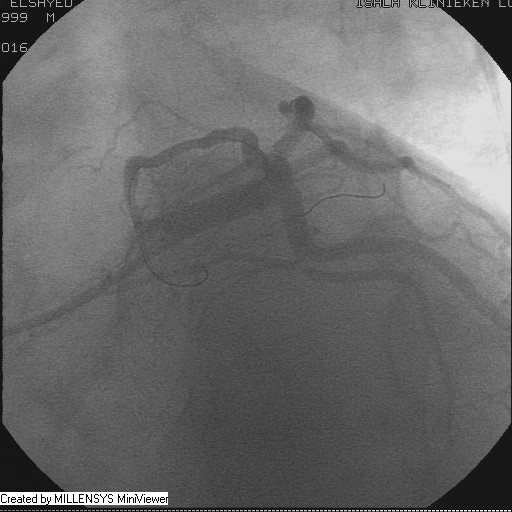

After crossing with the PTCA wire, a minimal flow started to appear in the diagonal branch (Figure 6), then LAD was wired, then a 2x15mm Balloon was used to pre-dilate (Figure 7,8), a big diagonal branch appeared with proximal thrombotic tight lesion (Figure 9), the diagonal angle to LAD was about 90 degree (Figure 10), so provisional stenting done to diagonal from its ostium with 3x20mm PROMUS ELEMENT PLUS DES (Figure 11,12), with good final result (Figures 13&14).

Figure 10